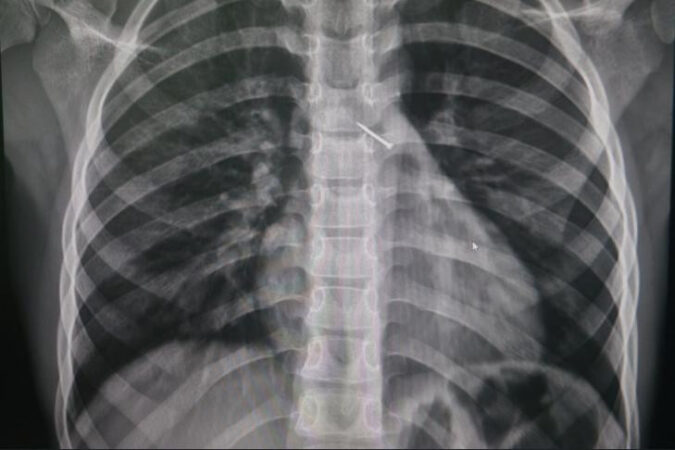

— Обследование показало, что канцелярская кнопка попала в бронхи, уперлась в одну из стенок и вызывала локальное воспаление. Опасный предмет успешно достали с помощью эндоскопических зажимов, — говорится в сообщении министерства здравоохранения Новосибирской области.